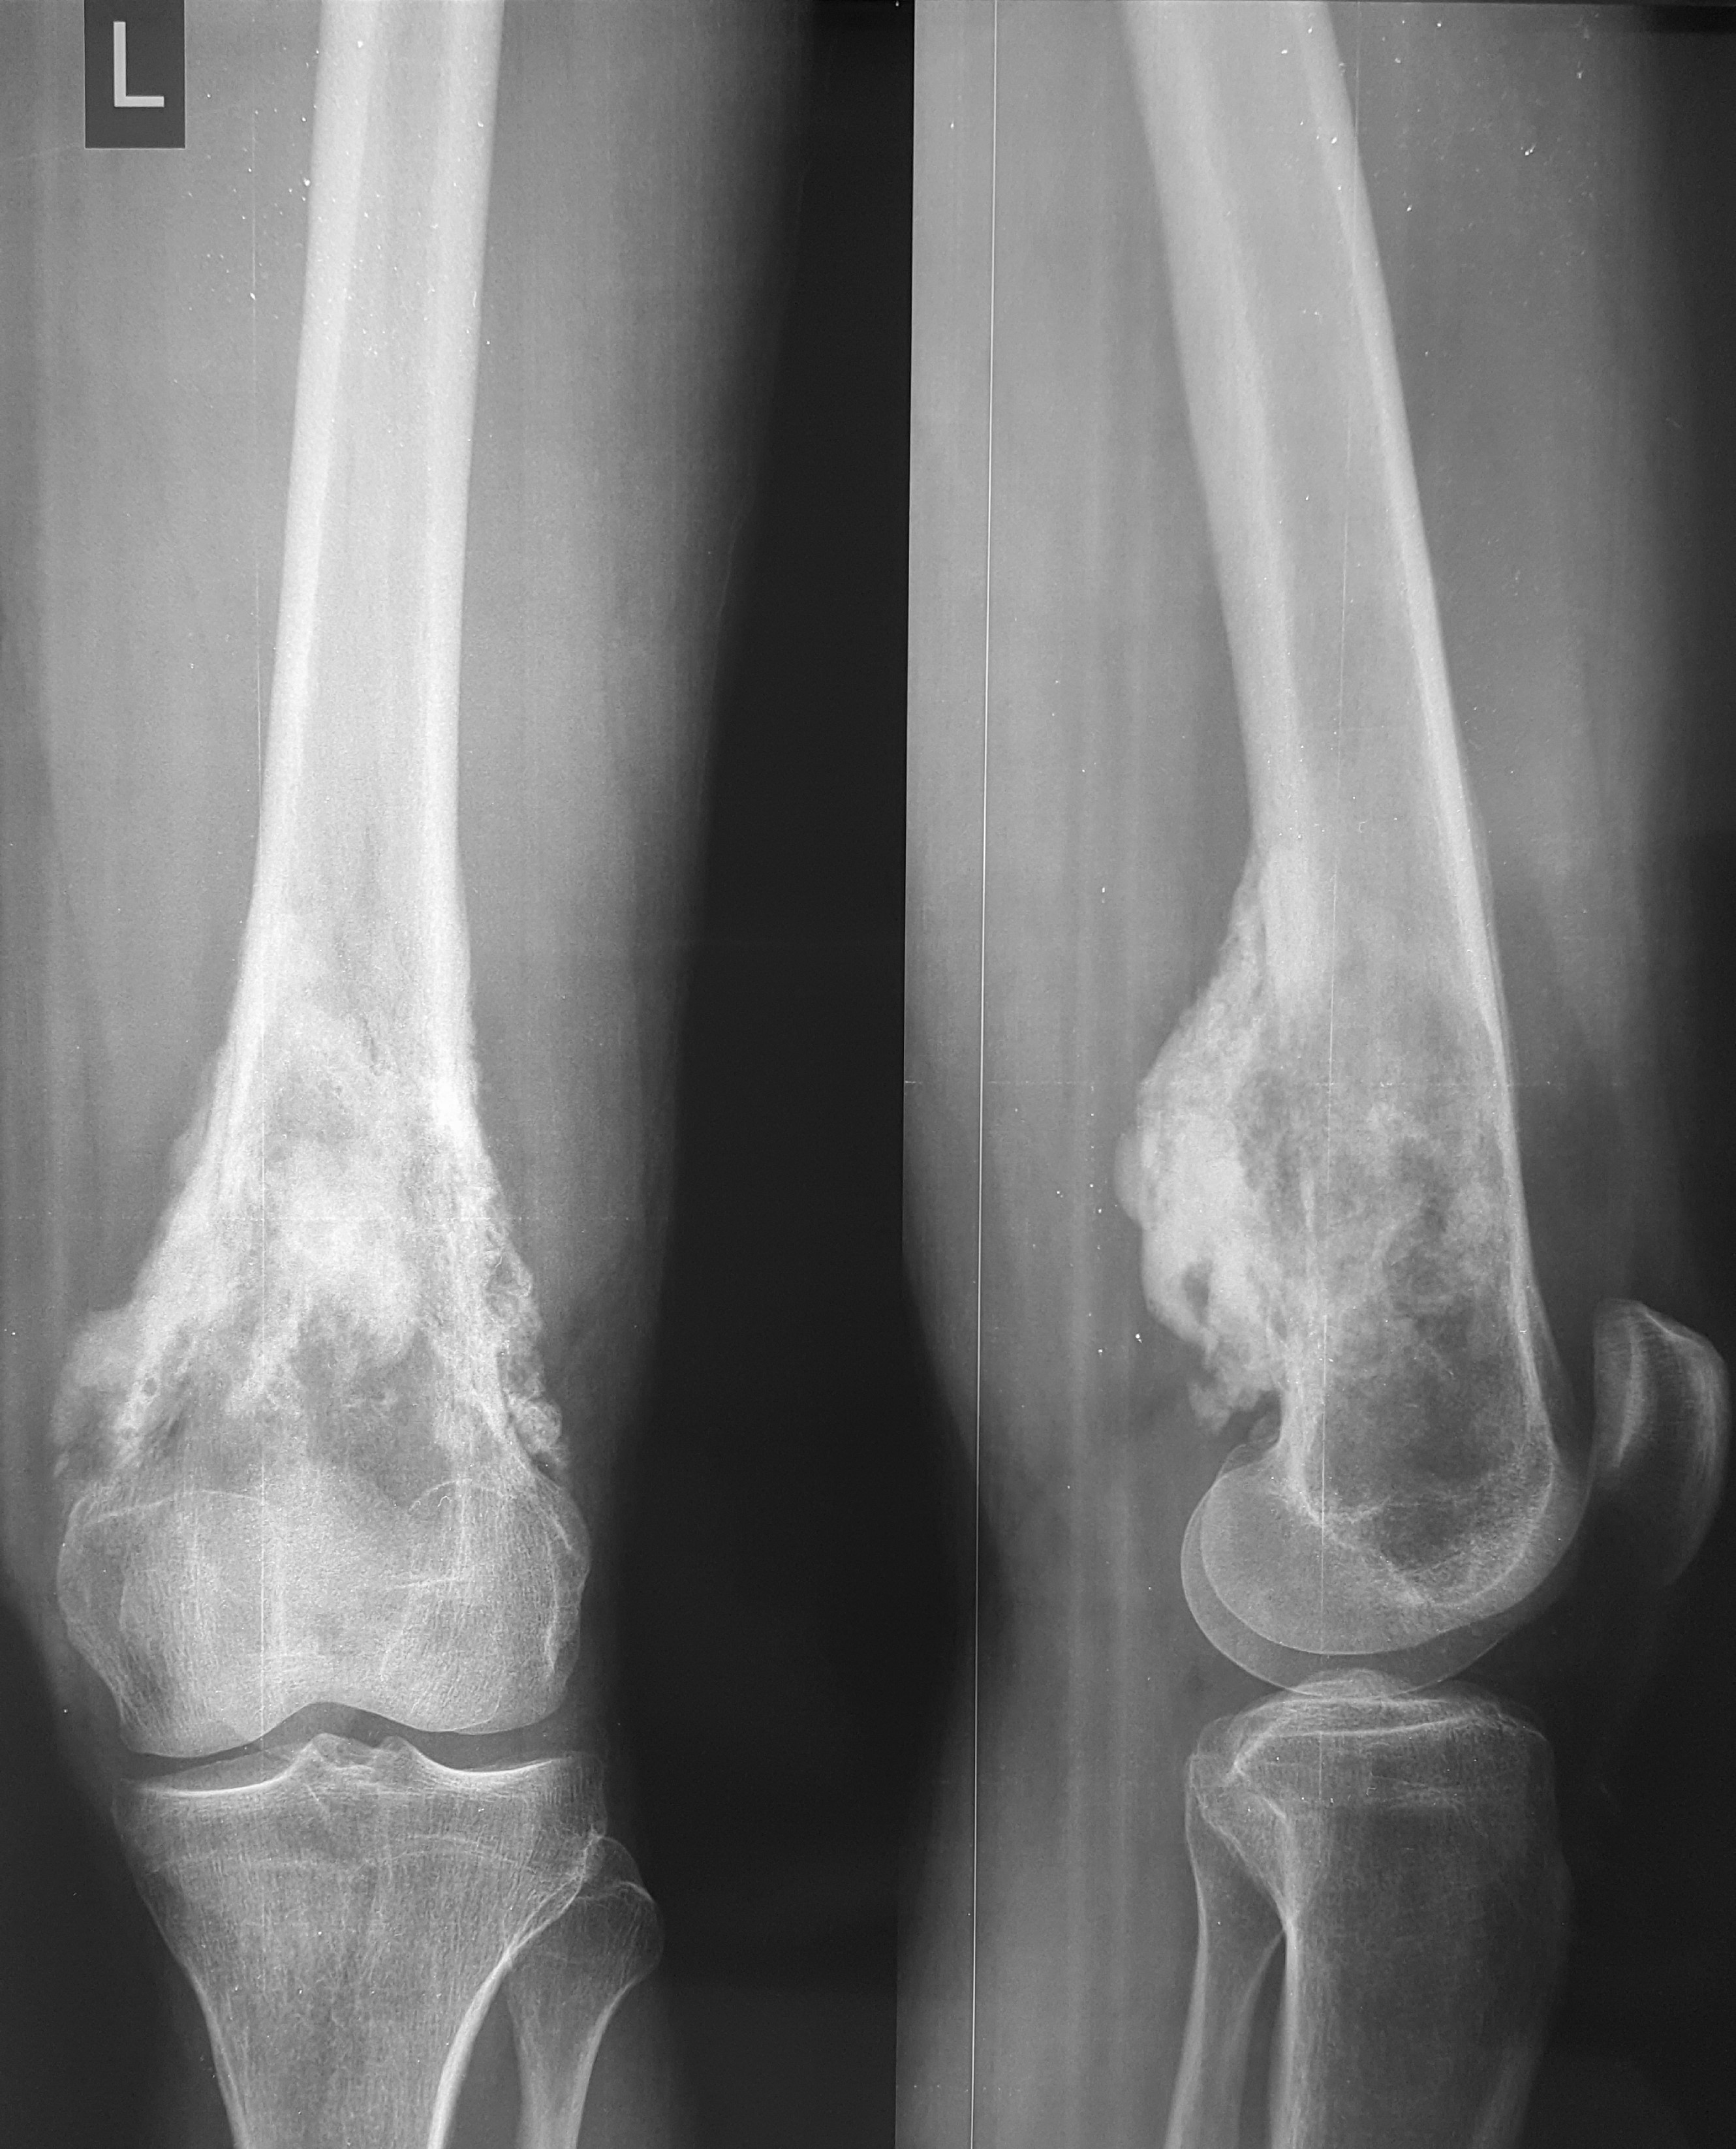

2. Остеосаркома большеберцовой кости

17-летний юноша обратился в МЦ ''Наири'' с жалобами на боли в области коленного сустава. После прохождения обследования у пациента была диагностирована остеосаркома большеберцовой кости.

До операции